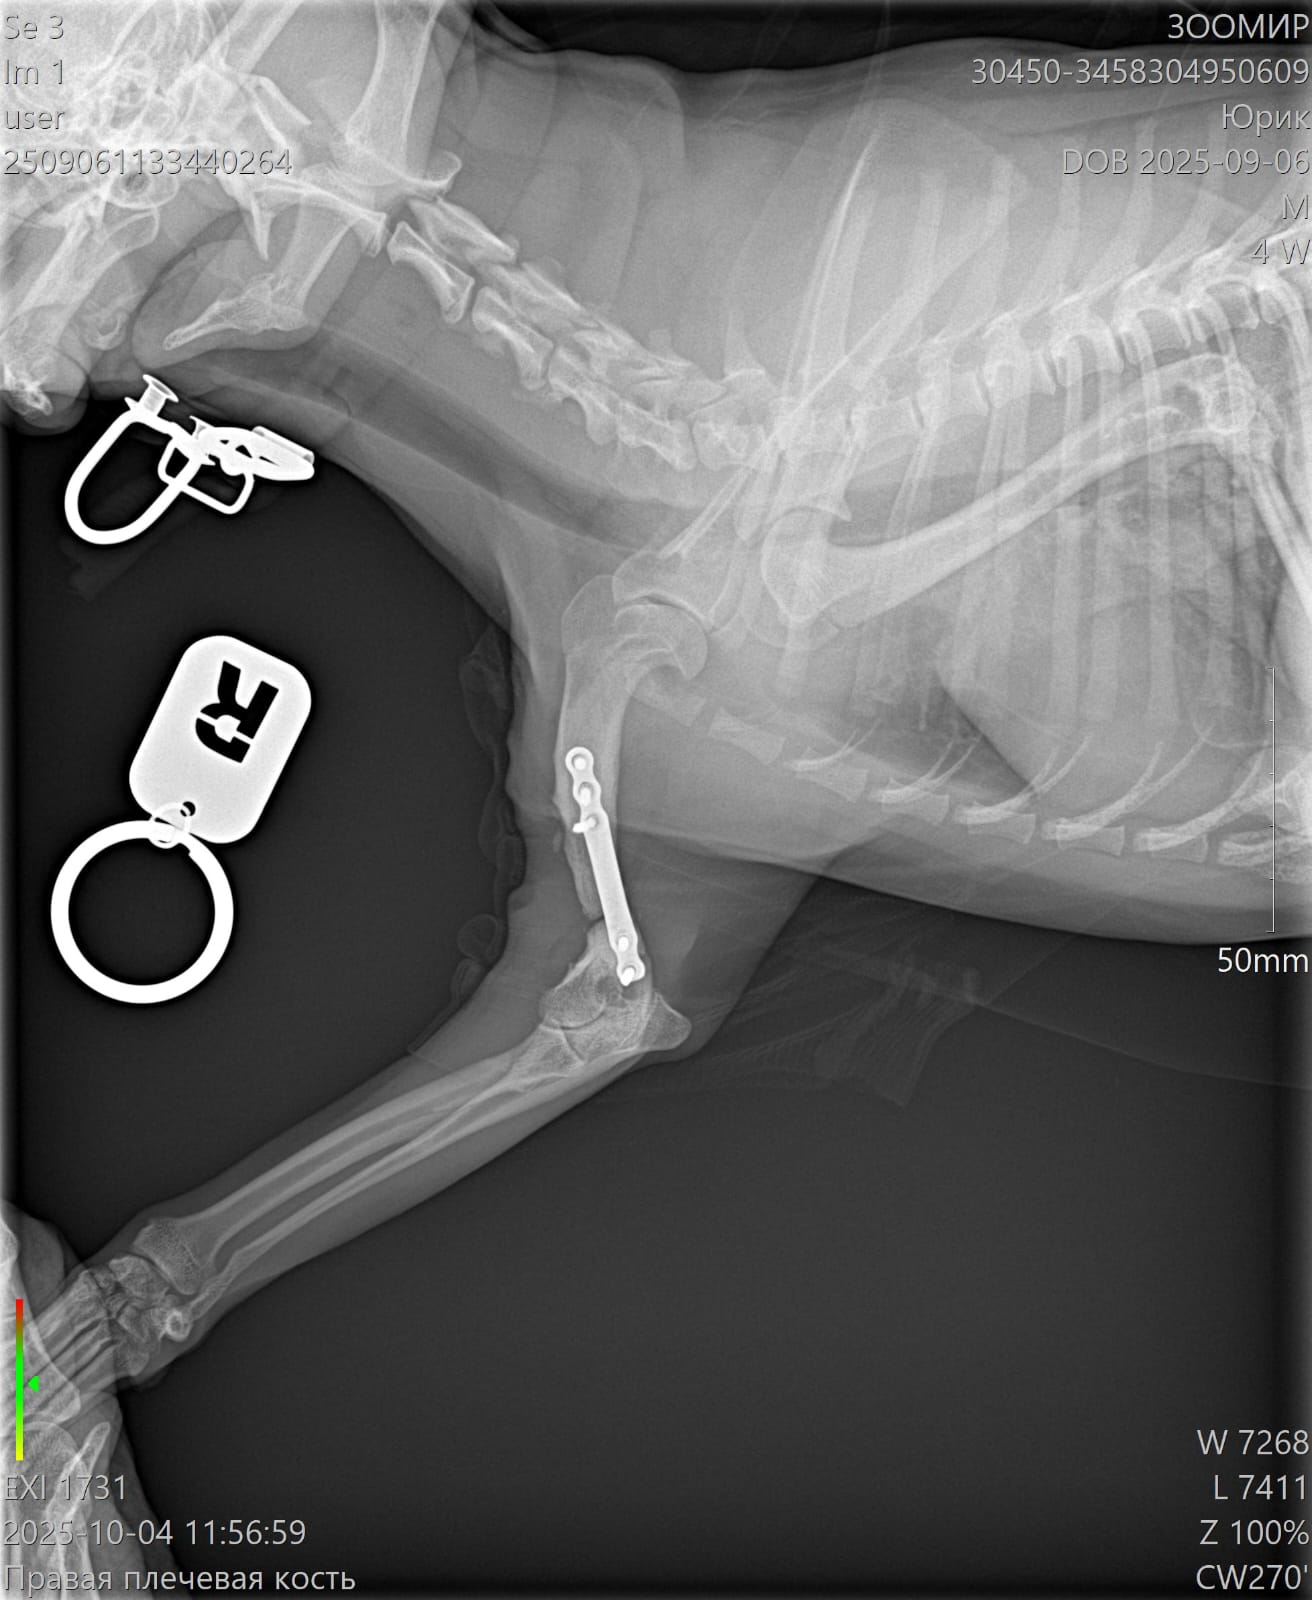

Сделали контрольный рентген - пока мозоли не видно:((((

Теперь через месяц.

Лапой на ровном немного пользуется. Но это за счет пластины.

Рентген